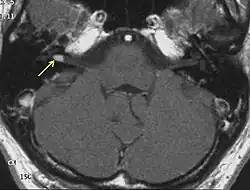

- jednostronne (6%) i obustronne (85%)[8] schwannomata nerwu przedsionkowego (VS). Schwannoma mogą też wychodzić z innych nerwów czaszkowych, częste są schwannoma nerwu okoruchowego i trójdzielnego (29% pacjentów, zazwyczaj obustronnie; rzadko wymaga leczenia chirurgicznego);

- Obustronne schwannoma nerwu przedsionkowego potwierdzone histopatologicznie lub widoczne w MRI ze wzmocnieniem kontrastowym, lub